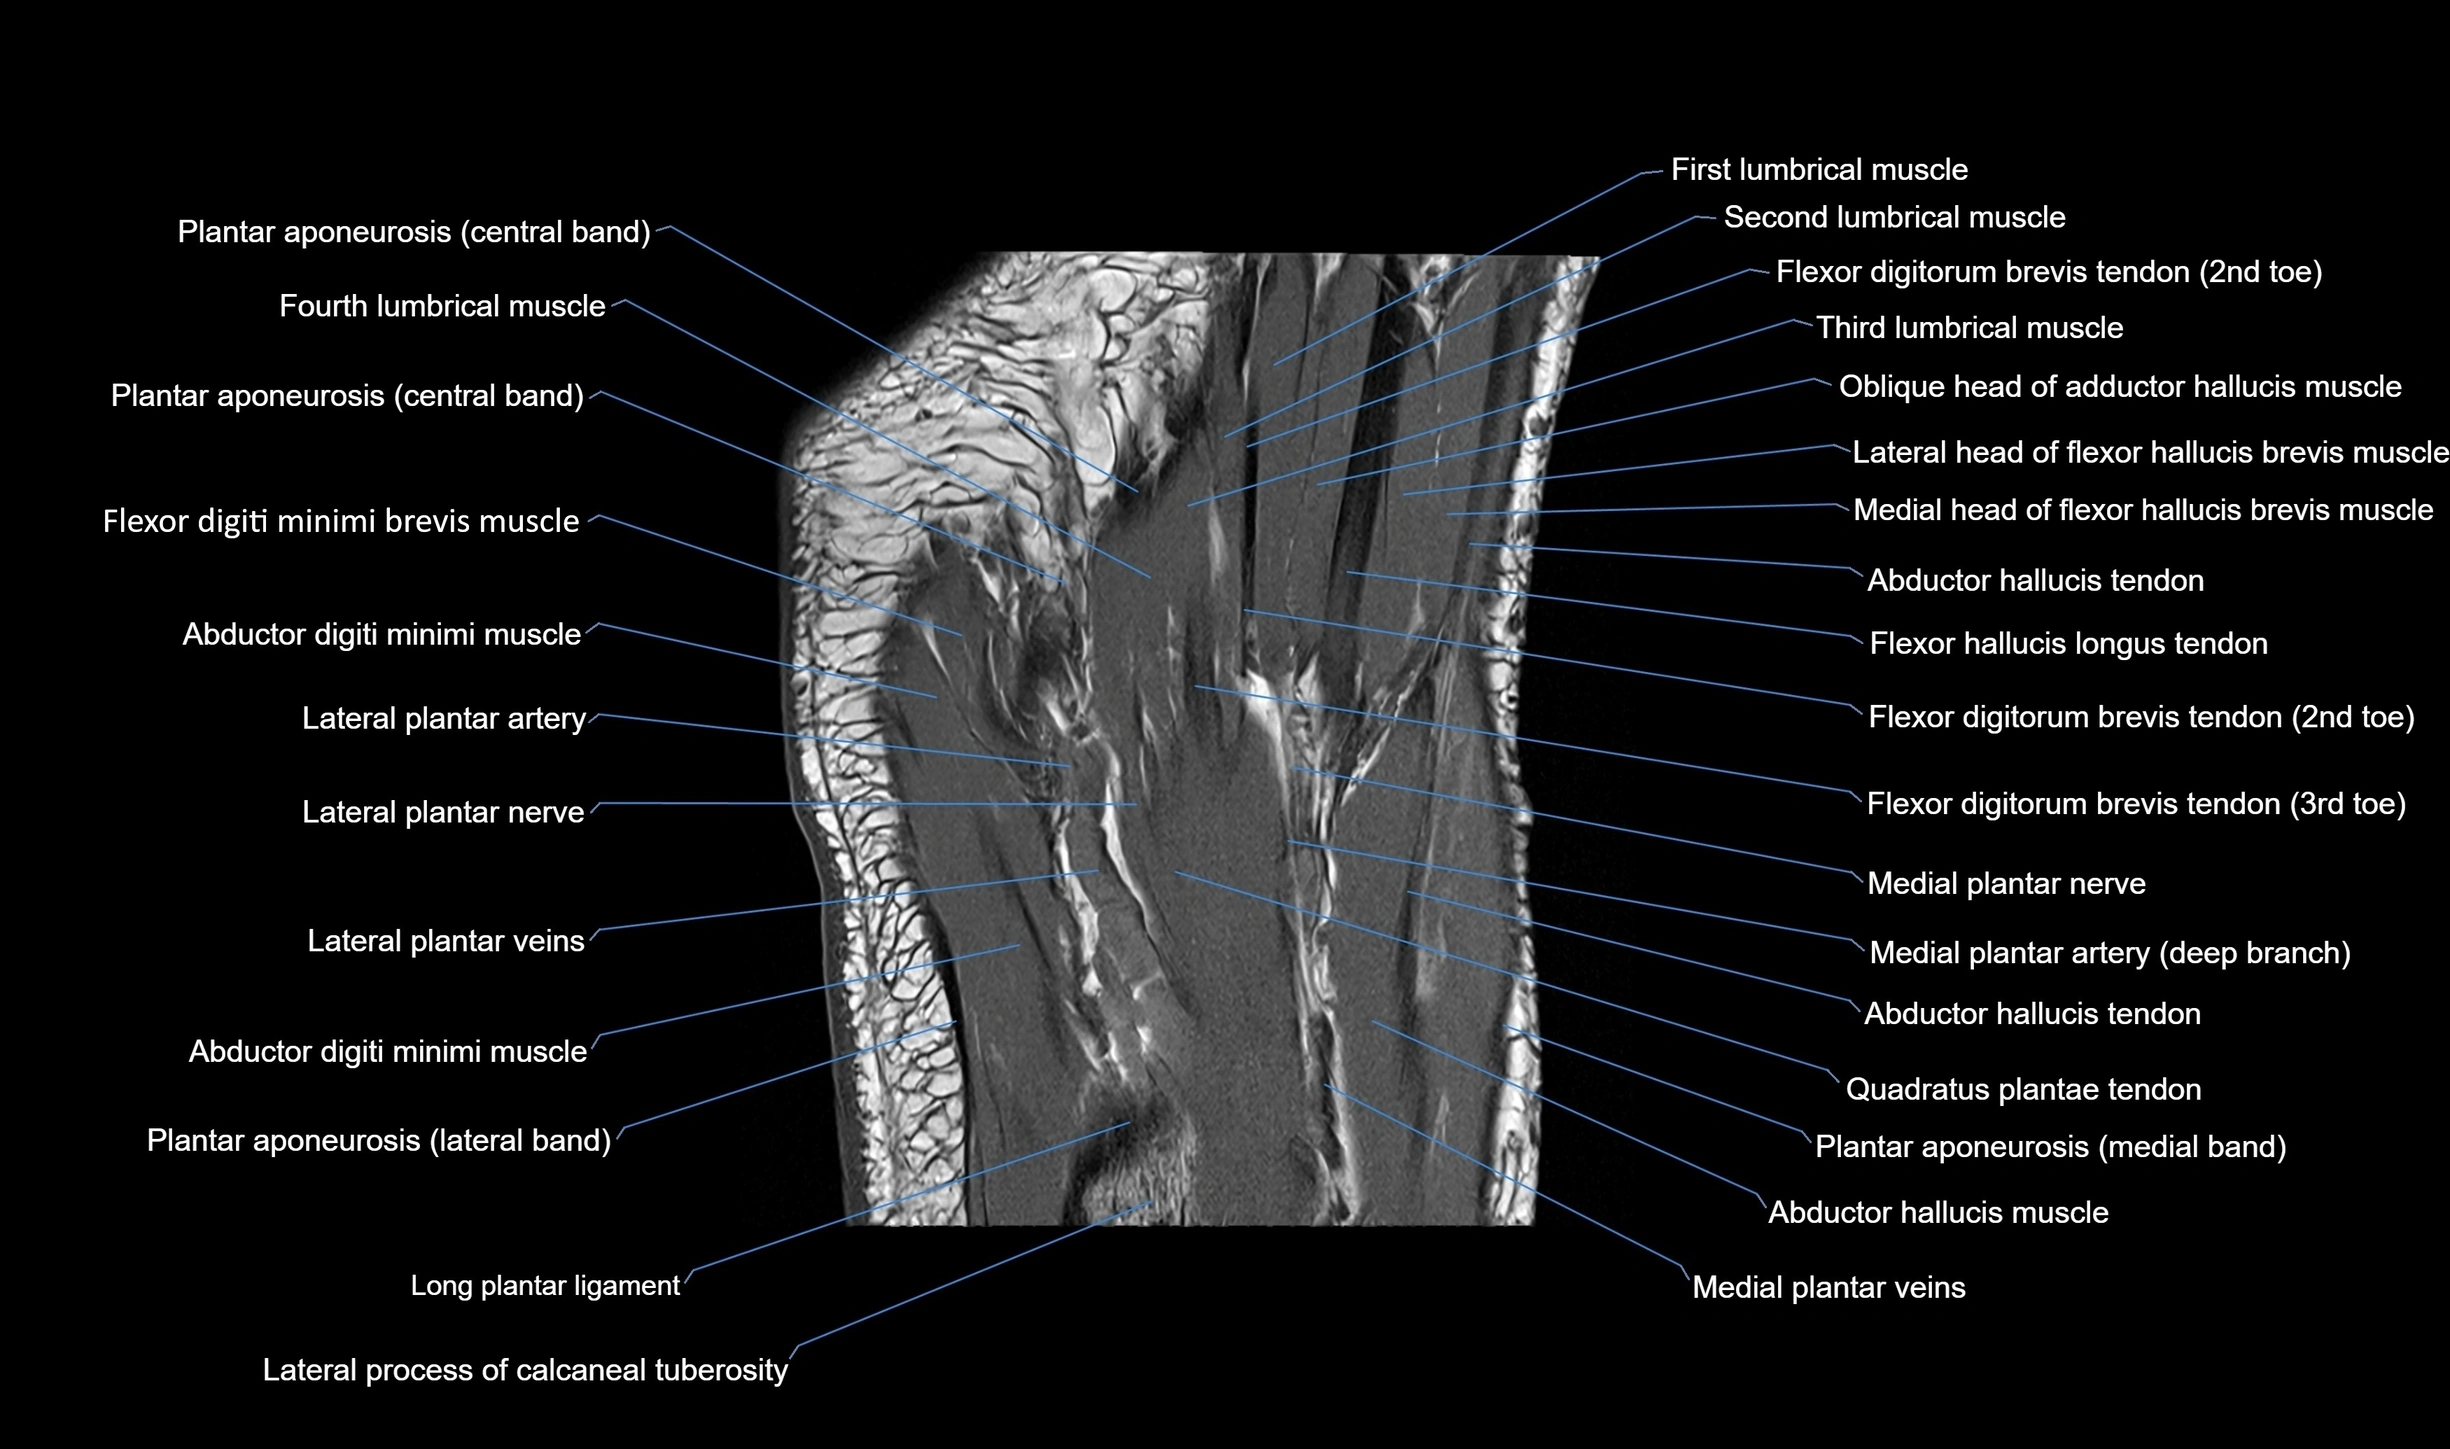

MRI image